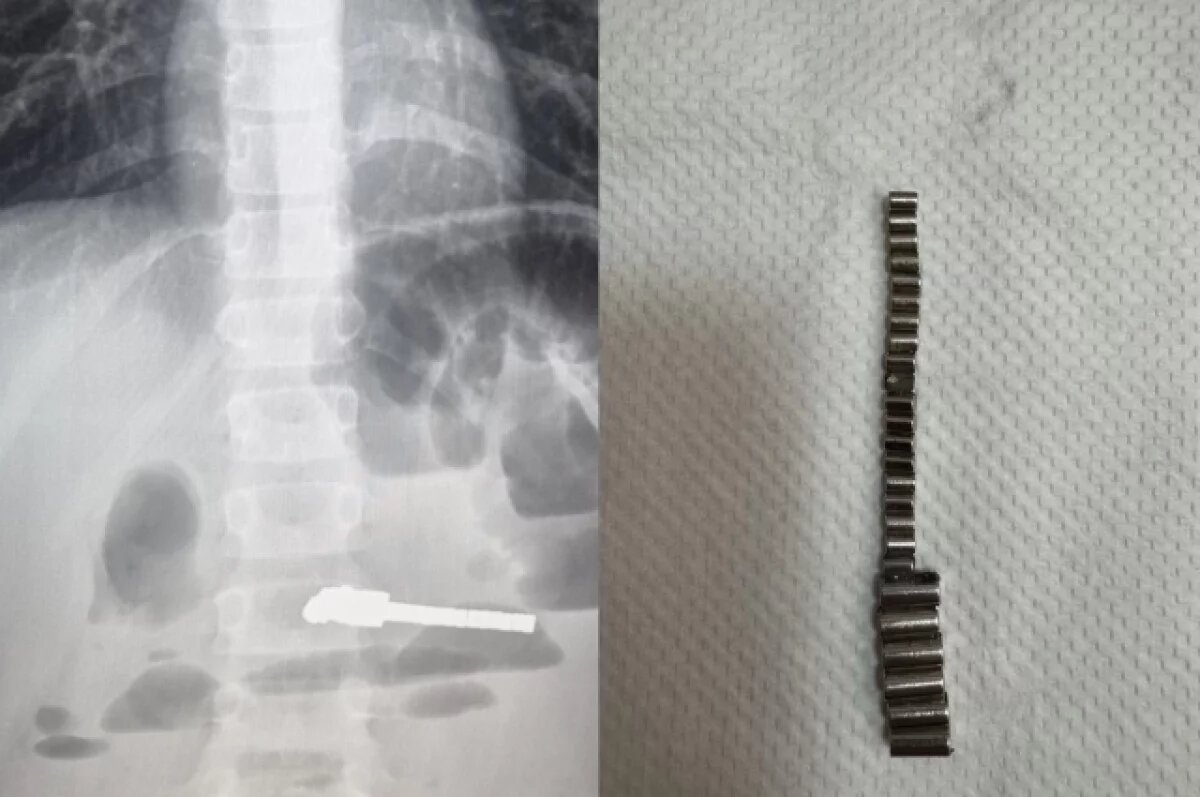

Как сообщила главный врач больницы Евгения Аверкина, ребёнок поступил в приёмное отделение с жалобами на сильные боли в животе и многократную рвоту. Рентгеновское обследование показало наличие множества инородных предметов в кишечнике и признаки развивающейся кишечной непроходимости.

Несмотря на сложность ситуации, хирургическое вмешательство прошло успешно. Все 25 магнитных элементов были удалены, и жизни ребёнка теперь ничего не угрожает.